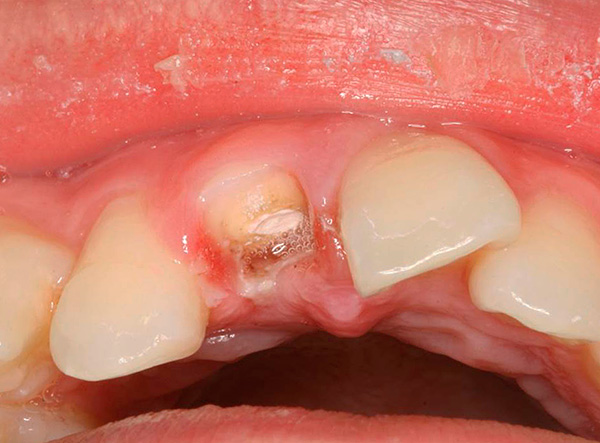

Le fotografie seguenti mostrano l'estrazione del dente, la cui parte della corona viene distrutta quasi al livello delle gengive:

Dalla pratica del dentista

Nei pazienti in età adulta (dai 40 anni in poi), la rimozione delle radici dei denti marci nella stragrande maggioranza dei casi non presenta particolari difficoltà, perché sullo sfondo dell'atrofia alveolare, una diminuzione dell'altezza delle partizioni e il processo infiammatorio vicino alle radici, il corpo “rifiuta” stesso, per così dire, pertanto, c'è spesso la loro mobilità in un modo o nell'altro. I professionisti sono ben consapevoli del fatto che più il paziente è anziano, meglio è, poiché la rimozione insieme all'anestesia richiede quasi sempre alcuni minuti, per la gioia del paziente e del medico.